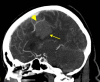

Cerebrovascular pseudoaneurysm development and rupture is a rare, delayed sequelae of trauma. We present a case of a female patient in her sixties who presented after a fall without evidence of vascular injury on imaging. However, after one week, repeat imaging due to an abrupt change in mental status revealed a ruptured pseudoaneurysm, which was treated with a combination of coil embolization and open surgical evacuation of associated intracranial hematoma. This case illustrates the importance of continued surveillance beyond the acute traumatic period to identify late-onset complications in trauma patients requiring emergent treatment.